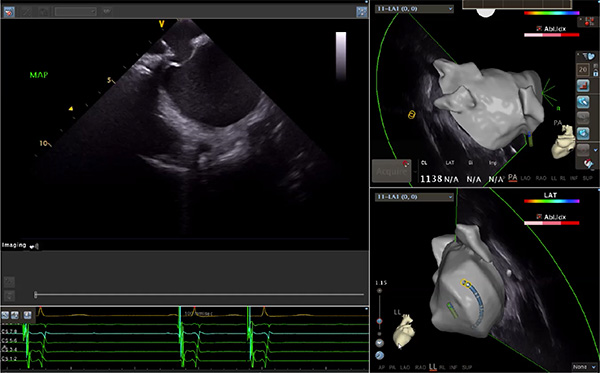

超聲心動(dòng)圖技術(shù)包括常規(guī)經(jīng)胸超聲(TTE)、經(jīng)食管超聲(TEE)、心腔內(nèi)超聲(ICE)、超聲聲學(xué)造影(MCE)、三維超聲心動(dòng)圖等,ICE是一種新興技術(shù)——將微型的換能器安裝在心導(dǎo)管的尖端,經(jīng)由外周血管輸送至心腔內(nèi)部,換能器發(fā)射聲波,對(duì)心臟及其鄰近組織進(jìn)行實(shí)時(shí)高質(zhì)量成像和(或)血流動(dòng)力學(xué)測(cè)定的超聲成像技術(shù)?;诓煌募夹g(shù)原理,心腔內(nèi)超聲導(dǎo)管被分為兩類(lèi):機(jī)械旋轉(zhuǎn)式超聲導(dǎo)管和相控陣超聲導(dǎo)管。目前,臨床上主要應(yīng)用的是相控陣超聲導(dǎo)管,ICE成像通過(guò)術(shù)者旋轉(zhuǎn)導(dǎo)管及操縱導(dǎo)管手柄上的兩個(gè)旋鈕來(lái)完成。

ICE門(mén)檻高、集成了超聲和圖像處理最前端的技術(shù),是當(dāng)前內(nèi)窺超聲方向最挑戰(zhàn)的領(lǐng)域。不同于傳統(tǒng)接觸式三維重建方法會(huì)產(chǎn)生假腔,影響術(shù)者對(duì)靶點(diǎn)或結(jié)構(gòu)的判斷,心腔內(nèi)超聲(ICE)可直接顯示心臟結(jié)構(gòu),有助于理解心臟內(nèi)各部位之間的解剖關(guān)系,不僅具有實(shí)時(shí)成像、并發(fā)癥監(jiān)測(cè)以及良好的耐受性,同時(shí)以股靜脈入路,無(wú)需全麻或深度鎮(zhèn)靜,日益成為心臟介入手術(shù)中重要輔助工具,被譽(yù)為心臟介入醫(yī)生的“黃金眼”。心腔內(nèi)超聲可用于多種心臟介入手術(shù),潛在患者群體龐大,動(dòng)脈網(wǎng)測(cè)算我國(guó)心腔內(nèi)超聲導(dǎo)管市場(chǎng)空間或?qū)⒊?00億元,具有廣闊前景。

隨著心腔內(nèi)超聲的應(yīng)用更廣,性能也在逐漸優(yōu)化,已從二維成像轉(zhuǎn)變?yōu)?strong>三維成像,極大增強(qiáng)了引導(dǎo)及可視化能力。二維心腔內(nèi)超聲支持雙平面或三平面成像,可顯示兩個(gè)或三個(gè)不同的平面視圖,但醫(yī)生需將這些圖像在腦海中重新構(gòu)建為三維解剖結(jié)構(gòu)。三維心腔內(nèi)超聲則可直接呈現(xiàn)三維解剖結(jié)構(gòu)圖,便于醫(yī)生更輕松地開(kāi)展手術(shù)。按照產(chǎn)品發(fā)展方向,預(yù)計(jì)心腔內(nèi)超聲還將向更清晰、精準(zhǔn)、多功能等方向發(fā)展。